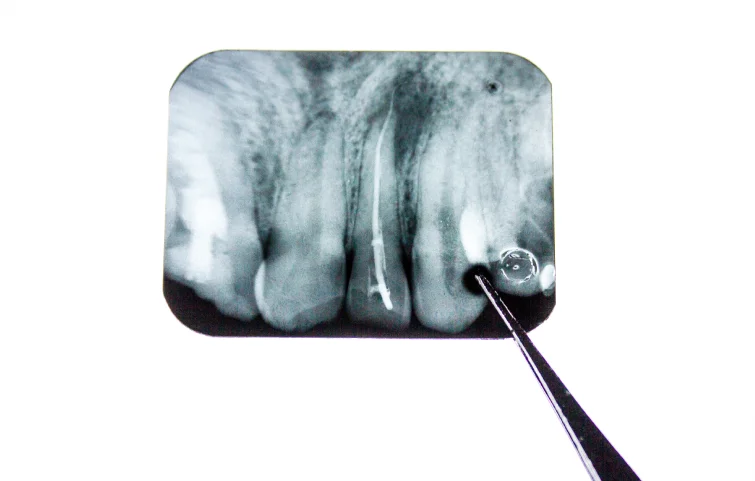

On physical exam, any visible or palpable masses, intraoral swellings, or displaced teeth are noted. Imaging is critical in evaluating the lesion's size, location, and characteristics. A panoramic X-ray (orthopantomogram) is usually the first step to detect radiolucent or radiopaque lesions suggestive of cysts or tumors. CT scans and MRI are often required for detailed assessment of bony expansion, cortical involvement, and soft tissue extension.

Cone-beam CT (CBCT) offers high-resolution images of localized jaw structures, making it ideal for pre-surgical planning. In suspected aggressive or malignant lesions, MRI helps assess infiltration into surrounding tissues. For definitive diagnosis, biopsy is essential. It can be incisional (sample portion) or excisional (complete removal) and is followed by histopathological examination to determine the exact nature—e.g., odontogenic keratocyst, ameloblastoma, or carcinoma.